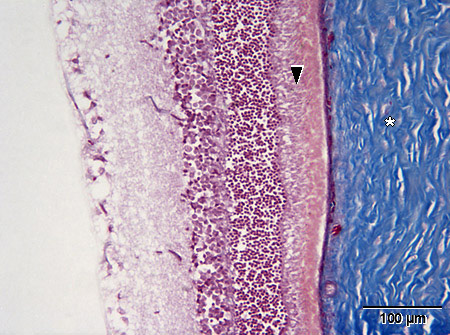

Valomikroskooppikuva rotan silmän verkokalvosta (Milliganin sidekudosvärjäys).

tähti = kovakalvo, skleera

nuolenpää = sauva- ja tappisolukerros